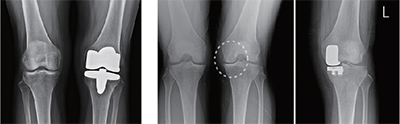

무릎인공관절치환술

• 무릎 관절염이 심한 경우, 다리가 ㅇ자로 휜 경우 보행 시 통증이 심하며 골반이나 허리통증까지 유발하기도 합니다.

• 이런 경우 인공관절수술을 통해 통증해소, 다리모양 교정등의 효과를 얻을 수 있습니다.